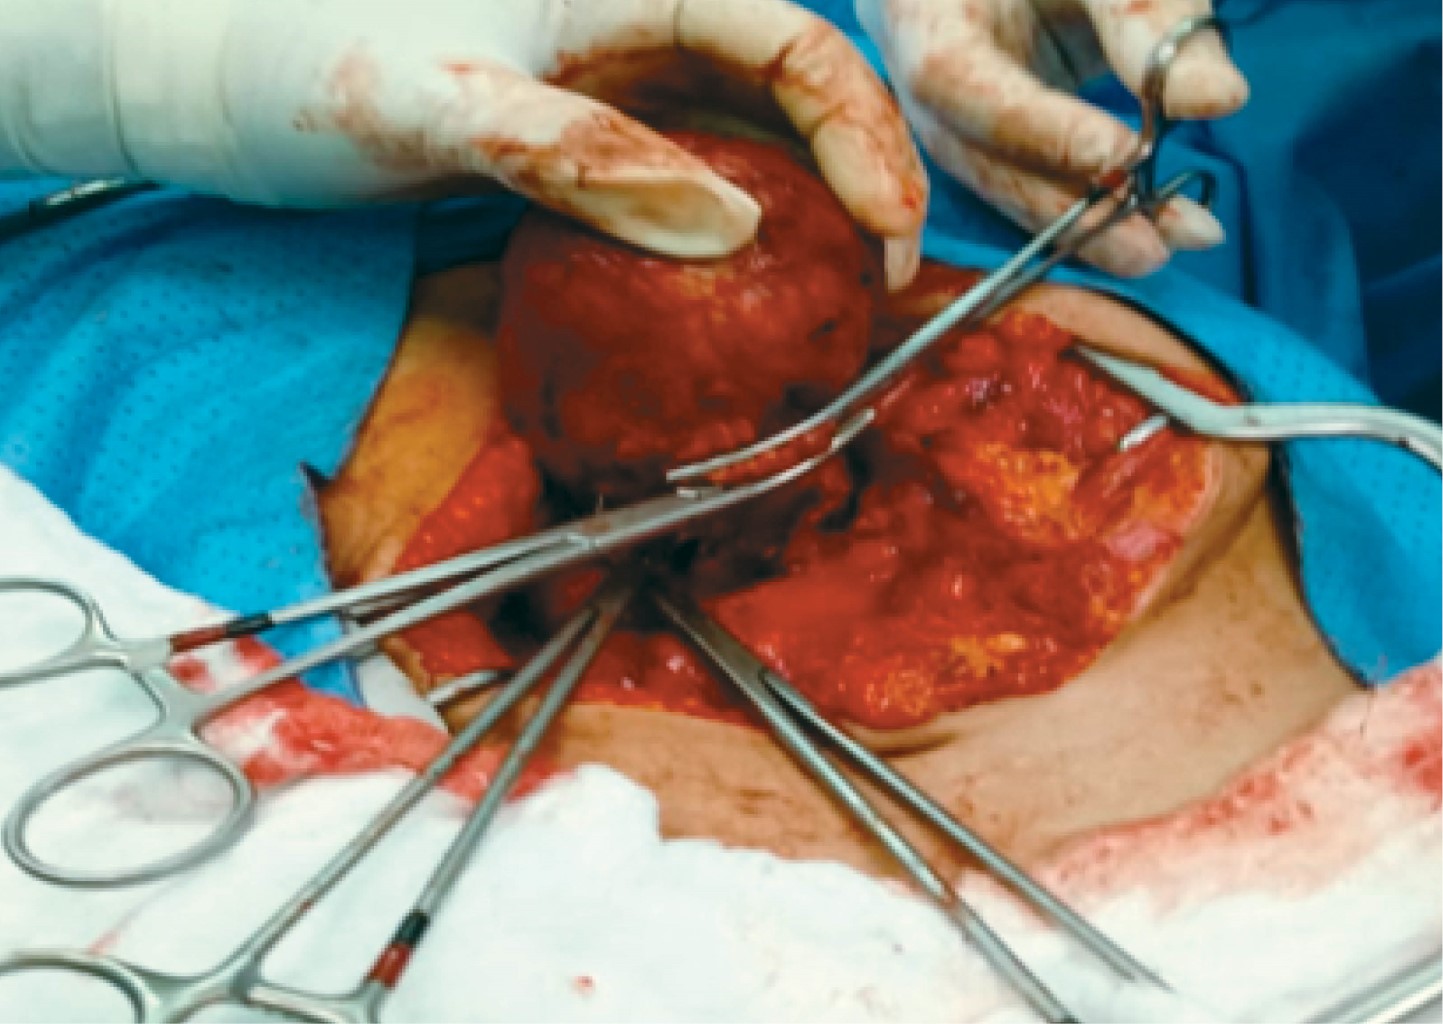

La paciente fue sometida a laparotomía exploradora donde se identifica masa tumoral de aproximadamente 6 × 8 cm a nivel de la cabeza del páncreas adosada a la segunda porción del duodeno, por lo que se procede a realizar enucleación por medio de disección de segunda porción de duodeno y porción transpancreática involucrando conducto pancreático principal, se realiza tutorización del mismo con sonda Nélaton No 12, exteriorizándola a través de segunda porción del duodeno hacia la pared abdominal a la altura del flanco derecho, siendo fijada con sutura de polidioxanona PDX 3.0 (Figuras 2, 3 y 4).

Macroscópicamente los tumores son de aspecto esferoidal o elípticos, bien circunscritos, compuestos de una cápsula con zonas hemorrágicas y necróticas en su interior en 50% de los casos, la presencia de calcificaciones y septos muy friables se observa con menor frecuencia.4,5,7 La forma macroscópica de nuestro caso era quística, medía 8 × 4.5 × 3 cm con superficie lisa color rosado rojizo que eliminaba material sanguinolento y tejido degenerativo.

Figura 3

Figura 4